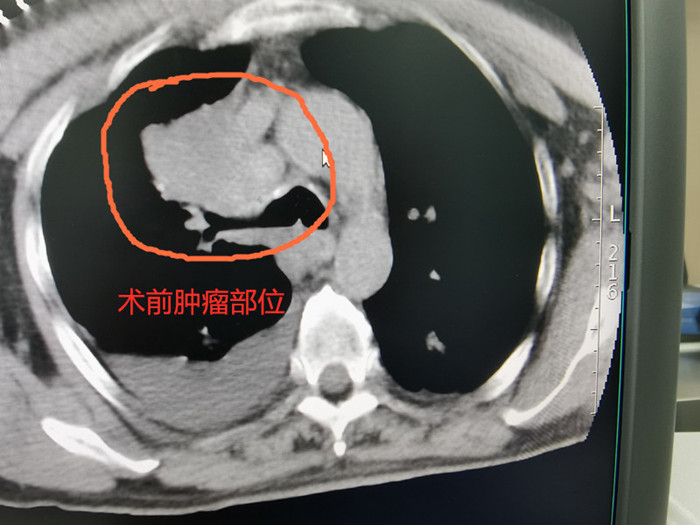

68歲的吳老伯因確診右上肺鱗癌收治入院,腫瘤侵犯胸膜及上腔靜脈,失去手術(shù)根治切除的機(jī)會(huì),放化療效果也不理想。經(jīng)過(guò)多次討論,腫瘤放療團(tuán)隊(duì)決定為他實(shí)施共面模板引導(dǎo)下放射性粒子植入術(shù)。

術(shù)前CT